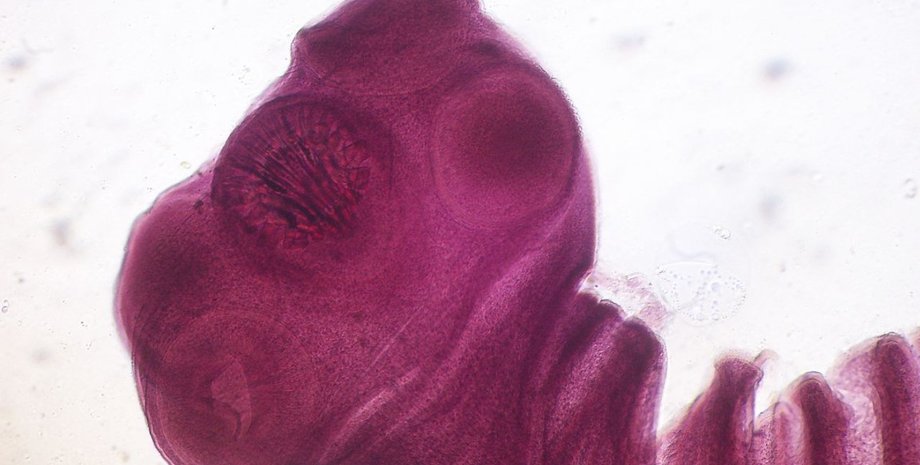

ленточные черви, свиной цепень

Свиные цепни способны проникать в мозг человека | Фото: Wikipedia

Как только ленточный червь прикрепляется к стенке кишечника человека с помощью крючков и присосок, он растет и созревает, поглощая питательные вещества в человеческом кишечнике. По мере взросления червь образует сотни сегментов, известных как "проглоттиды", длиной в несколько миллиметров. При этом сам червь может достичь невероятных 4 метров в длину.

Спустя пару месяцев, так как ленточные черви являются гермафродитами, эти проглоттиды беременеют, а каждая из них содержит 300-500 семенников и три доли яичника. В результате при попадании в пищеварительный тракт каждая из них содержит от 50 до 60 тысяч оплодотворенных яиц. Эти яйца выводятся из организма в виде каловых масс размером с тыквенное семечко. К слову, у человека это может быть единственным признаком наличия инфекции.